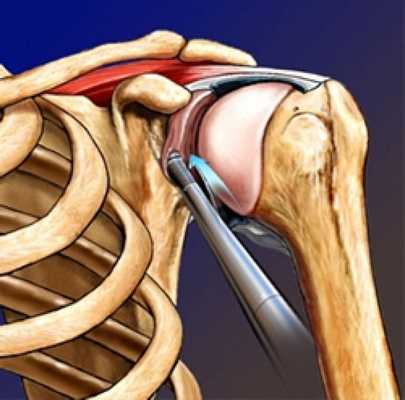

Для основной массы разрывов применяются современные технологии артроскопического шва. Артроскопия выполняется под эндотрахеальным наркозом, который может сочетаться с проводниковой анестезией нервов плечевого сплетения. На операционном столе уже под анестезией пациент укладывается в положение «пляжного кресла». Артроскопическое вмешательство подразумевает выполнение 4-5 проколов по 5мм по периметру плечевого сустава, в который вводится камера и микрохирургические инструменты. С их помощью производится декомпрессия сухожилия, очистка и расширение субаромиального пространства. Шов сухожилия выполняется после установки в головку плечевой кости специальных винтов (якорей) с прикрепленными к ним нерассасывающимися нитями. За счет нитей сухожилия прошиваются и фиксируются в головке плечевой кости.

Биодеградируемые импланты Титановые импланты